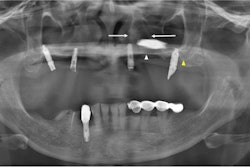

The retrospective study was conducted at a dental hospital in Hong Kong to determine whether impaction of a maxillary canine can be predicted using measurements made on a panoramic radiograph. Geometric measurements were made on 384 panoramic radiographs of patients with a unilaterally impacted maxillary canine (group 1) to characterize its presentation and compare them with the unaffected antimere (group 2).

In patients 8 years and older, the researchers found a "clinically discernible difference" of 4 mm between the mean distance of the tip of the impacted canine (group 1) and that of the antimere (group 2) from the occlusal plane (p < 0.05). They also found a statistically significant difference at the age of 9 years and beyond between the two groups according to the position in different sectors and according to the mean angle made with the midline (p < 0.05).